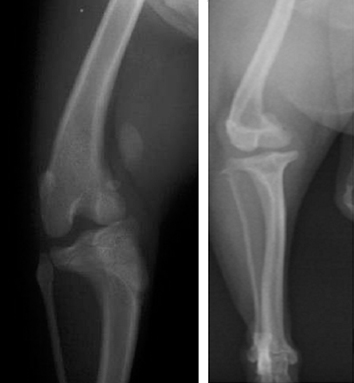

▲滑車溝が浅いGⅣのマルチーズ

▲滑車の溝を彫る形成術